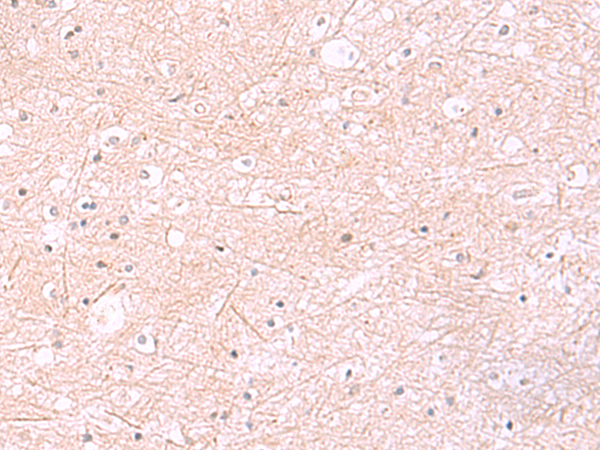

分类: 科研抗体货号: P10116别名: EWS; EWS-FLI1; bK984G1.4应用: WB,IHC反应种属: Human, Mouse